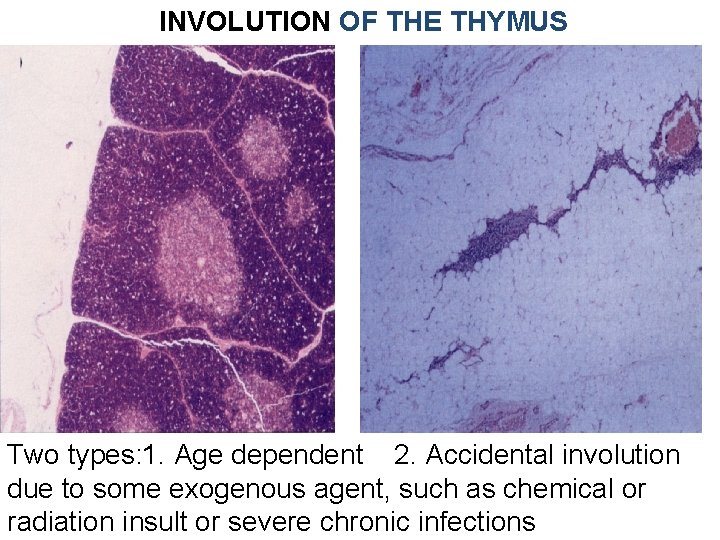

INVOLUTION OF THE THYMUS Two types: 1. Age dependent 2. Accidental involution due to some exogenous agent, such as chemical or radiation insult or severe chronic infections